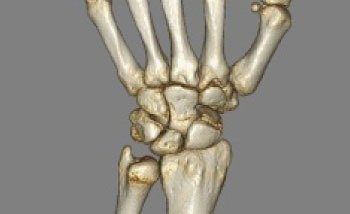

CT画像のデータから骨だけのデータだけを3次元表示しています。骨折や変形の全体像の把握に適しています。

手関節(3D)VR表示